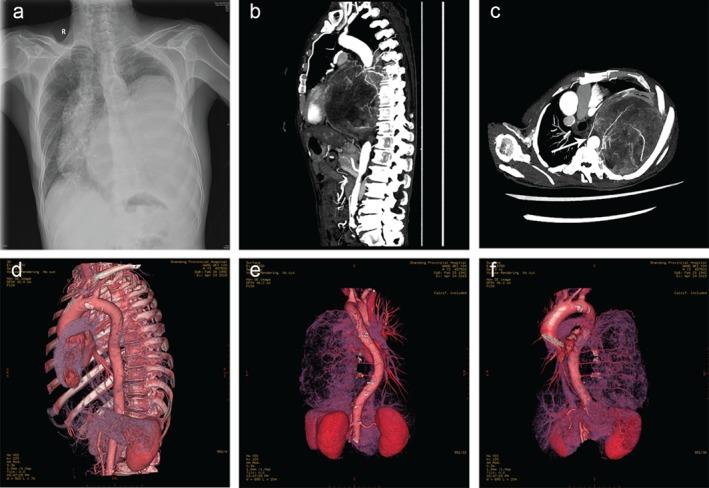

A giant thoracic neoplasm is extremely rare and poorly understood. Our systemic study introduced computed tomography angiography (CTA) with three-dimensional (3D) reconstruction imaging and evaluated correlations between imaging, pathology, and surgical management.

The clinical characteristics, imaging manifestations, and pathological types were complicated. Four patients underwent CTA with 3D reconstruction imaging and feeding vessels were found in three cases. Twenty-four selected patients accepted preoperative biopsy, eight of which were inconsistent with postoperative pathology. Complete resection was performed in 39 cases, 20 of which underwent extended excision. The median survival duration of all patients was 58 months (range 3.0-118.0). The one, three, and five-year survival rates were 86.0%, 64.4%, and 47.0%, respectively. Univariate analyses showed tumor size and resection status were prognostic factors for survival (P = 0.003 and P < 0.001, respectively).

A giant thoracic neoplasm should preferably be treated in experienced centers for precise diagnosis and optimal therapy schemes with comprehensive consideration of clinical characters, imaging manifestations, pathology, surgical management, and prognosis. Innovative CTA with 3D reconstruction imaging together with preoperative biopsy are feasible and effective in therapeutic decision-making and surgical planning. Complete surgical resection remains the mainstay of curative therapy for all resectable tumors.

巨大的胸部肿瘤极其罕见,目前了解甚少。我们的系统研究介绍了计算机断层血管造影(CTA)三维(3D)重建成像,并评估了影像学、病理学和手术管理之间的相关性。

患者的临床特征、影像学表现和病理类型复杂多样。4 例患者接受了 CTA 三维重建成像,其中 3 例发现了供血血管。24 例患者选择了术前活检,其中 8 例与术后病理不符。39 例患者行完全切除术,其中 20 例患者行扩大切除术。所有患者的中位生存时间为 58 个月(范围 3.0-118.0)。患者的 1、3 和 5 年生存率分别为 86.0%、64.4%和 47.0%。单因素分析显示肿瘤大小和切除状态是影响生存的预后因素(P=0.003 和 P<0.001)。

巨大的胸部肿瘤应在有经验的中心进行治疗,以便进行精确诊断和制定最佳治疗方案,综合考虑临床特征、影像学表现、病理学、手术管理和预后。创新的 CTA 三维重建成像与术前活检相结合,在治疗决策和手术规划方面是可行和有效的。完全手术切除仍然是所有可切除肿瘤的主要治疗方法。